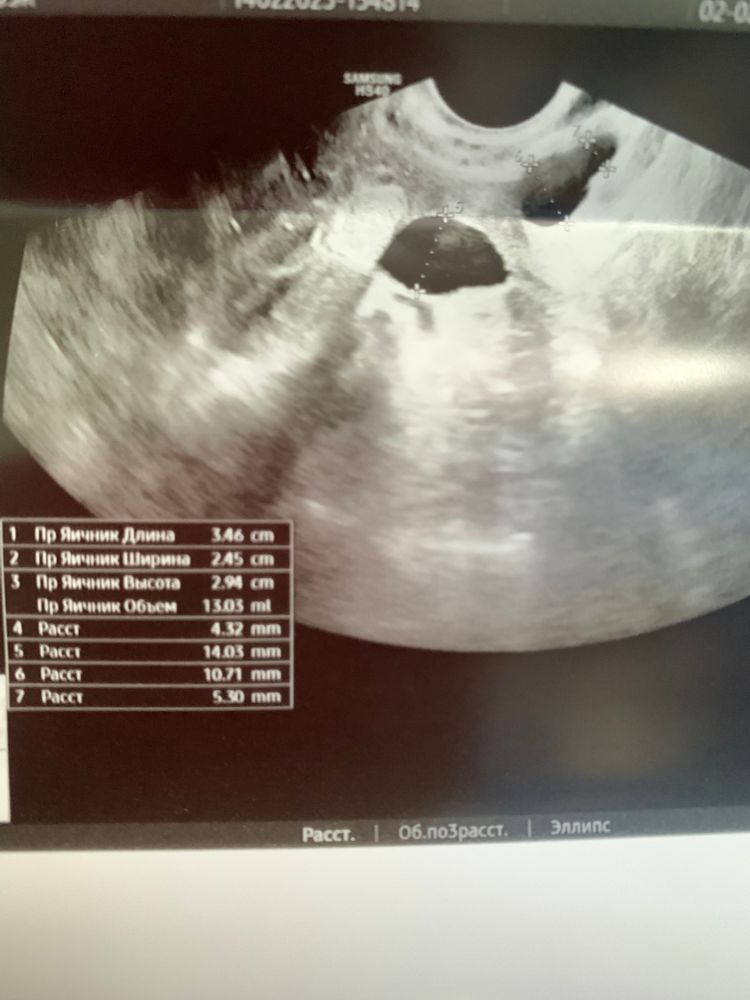

была недавно на узи, гинеколог сказала что есть желтое тело в правом яичнике, соответственно была овуляция. Только я н могу понять где именно желтое тело и что такое второе пятнышко, поясните пожалуйста,если не сложно. Буду безмерно благодарна🥺

Если вы выложили фото жёлтого тела, значит это узи яичника, рядом скорее всего зреет новый доминантный фаликул.

Я в таких случаях всегда сравниваю с фото, записи с такими же замерами на бумажке, там все пронумеровано. Если бы полное описание показали, было бы проще)